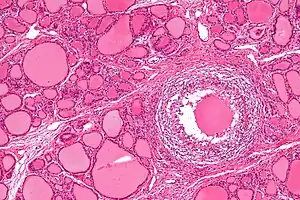

Micrograph showing a granuloma in subacute thyroiditis. H&E stain.

Patients will experience a hyperthyroid period as the cellular lining of colloid spaces fails, allowing abundant colloid into the circulation, with neck pain and fever. Patients typically then become hypothyroid as the pituitary reduces TSH production and the inappropriately released colloid is depleted before resolving to euthyroid. The symptoms are those of hyperthyroidism and hypothyroidism. In addition, patients may suffer from painful dysphagia. There are multi-nucleated giant cells on histology. Thyroid antibodies can be present in some cases. The clinical presentation during the hyperthyroid phase can mimic those of Diffuse Toxic Goiter or Graves' disease. In such cases, a radionuclide thyroid uptake and scan can be helpful, since subacute thyroiditis will result in decreased isotope uptake, while Graves' disease will generally result in increased uptake. Distinguishing between these two types of disease is important, since Graves' disease and Diffuse Toxic Goiter can be treated with radioiodine therapy, but subacute thyroiditis is usually self-limited and is not treated with radioiodine.